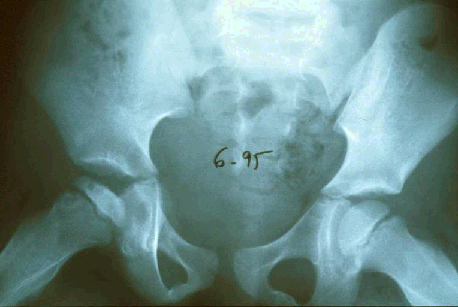

Illustration 4 : Évolution radiologique de l'ostéochondrite (d'après [3])

Illustration 5 : Signes radiologiques initiaux de l'ostéochondrite (d'après [3])